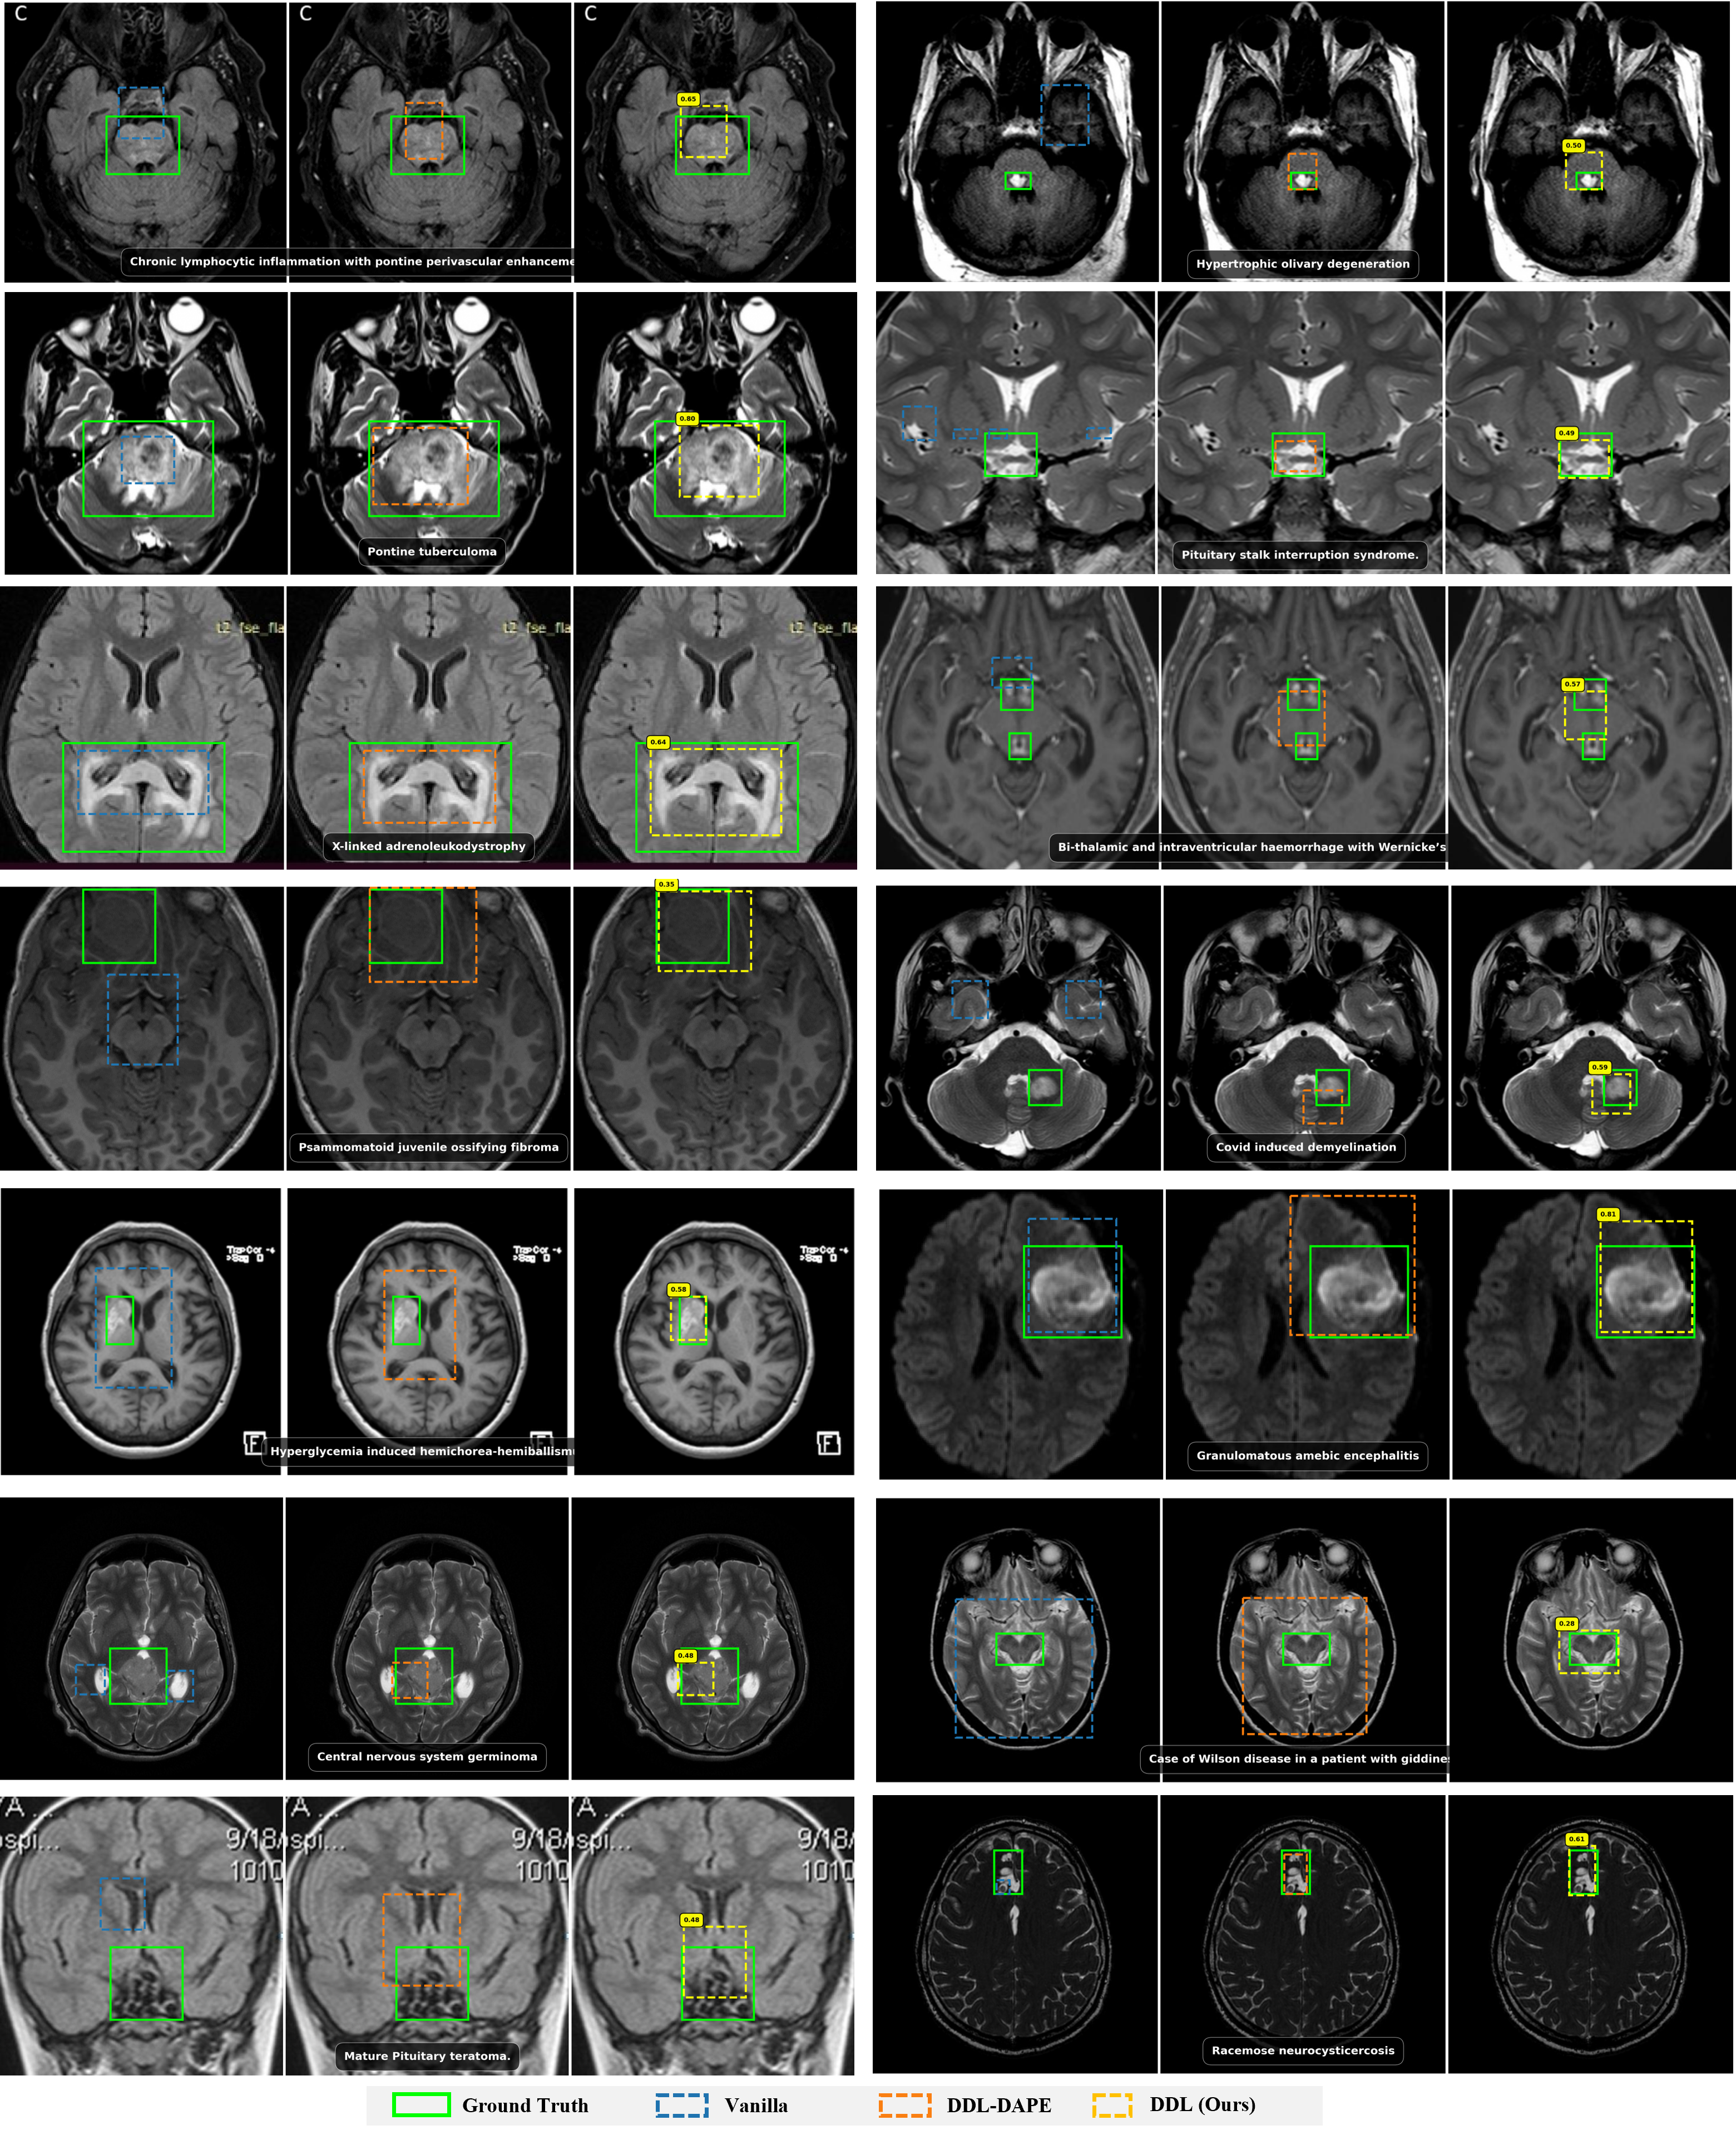

3B Results

Qwen2.5-VL-3B Grounding Performance